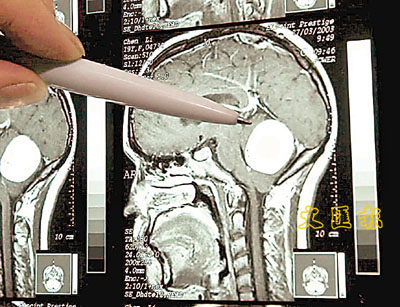

■由磁力共振掃描中,可清楚見到腦腫瘤的體積、位置等。